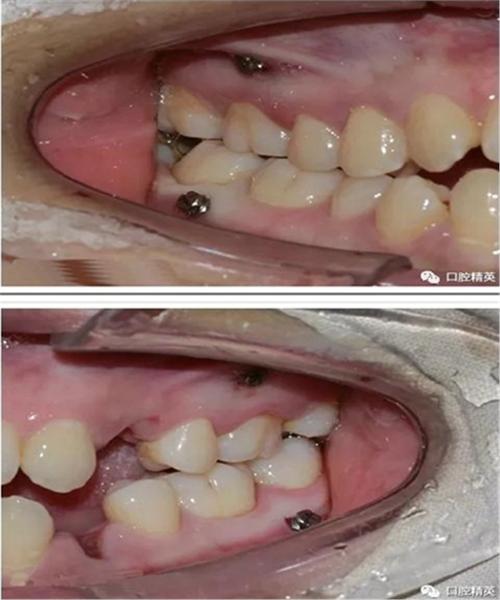

| 植入钉体 | 将微种植钉(钛合金)旋入骨孔,直至头部露出牙龈约1-2mm(便于后续挂橡皮圈)。 | 钉体植入后的三维位置图(展示与牙根、牙槽嵴的关系)。 |

- 植入位置:常见于上颌后牙区(颧牙槽嵴)、下颌后牙区(外斜线)、腭部(腭中缝)。